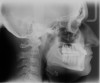

Fig 5. Preoperative cephalometric view highlighting maxillary deficiency, brachycephalic craniofacial phenotype, short upper face height, and maxillary retrognathia. Thin facial bone and proclined incisors are also noted.

Figure 5